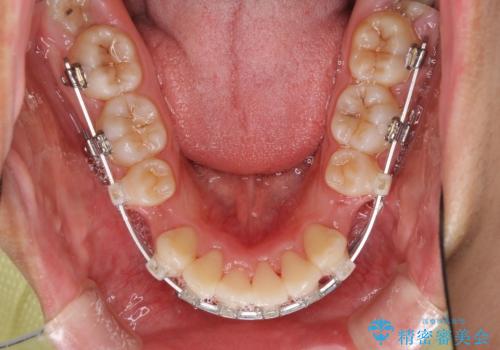

- クリアブラケット

- 上下の出っ歯を気にして来院された患者様です。

口元を積極的に引っ込めるために、上下左右の第一小臼歯を4本抜歯することとしました。

途中で来院されない時期があったため、期間が長引き、更には磨き残しが多かったことで虫歯が多く発現してしまいました。